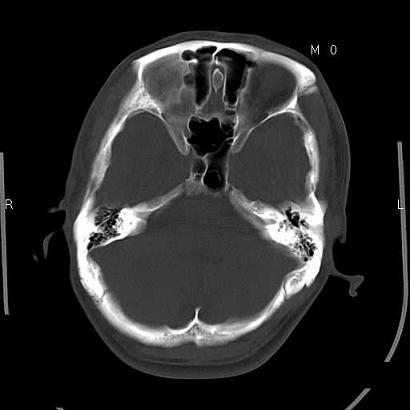

男,39岁,外伤来诊,老师们看看枕骨是什么病

枕骨静脉湖,常位于枕骨中线附近的板障间,多见于老年人,没得临床意义的。

枕骨粗隆部的舒松板障.

枕骨静脉湖,常位于枕骨中线附近的板障间.

蛛网膜颗粒压迹特点:位于中线两侧的颅骨圆形或类圆形低密度影,常多发,可融合,边缘有硬化缘,无软组织肿块。

枕内隆突左缘板障区示不规则囊状透亮区,颅骨内外板规整,无膨胀及缺损,周围无软组织肿块,考虑板障血管性病变,1.板障静脉湖,2.枕骨血管瘤(局部无膨胀性改变,无硬化环及钙斑影,故不太支持)。

蛛网膜颗粒压迹不会象这样有清晰的内板显示的!压迹压迹肯定是把内板压到板障里撒!各位老师同意不?